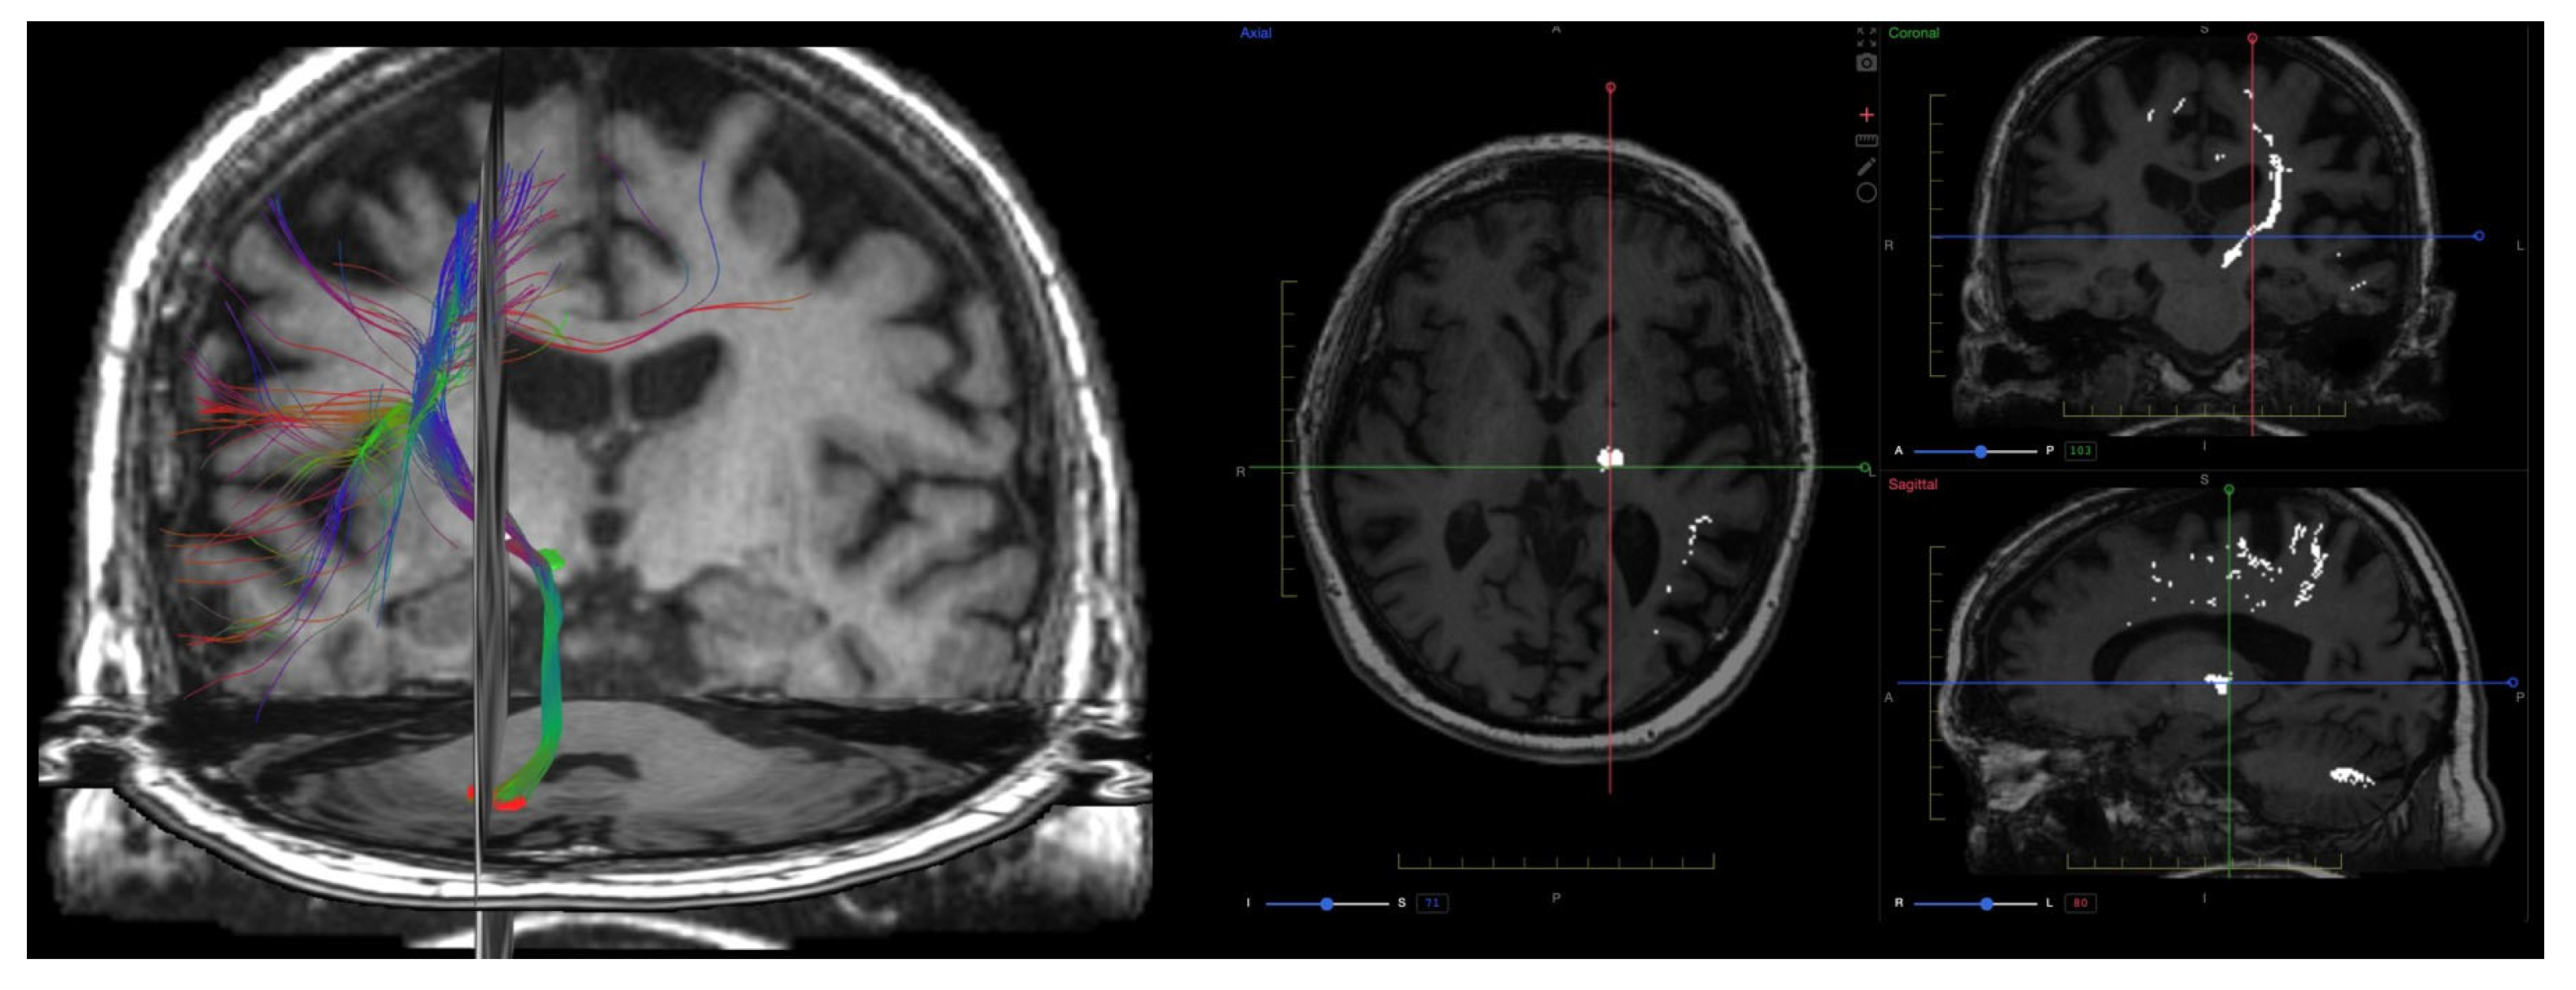

9. Diffusion Imaging (DWI, DTI, DKI)

9.4. Clinical Applications

- Christidi, F.; Karavasilis, E.; Samiotis, K.; Bisdas, S.; Papanikolaou, N. Fiber tracking: A qualitative and quantitative comparison between four different software tools on the reconstruction of major white matter tracts. Eur. J. Radiol. Open 2016, 3, 153–161. [Google Scholar] [CrossRef]